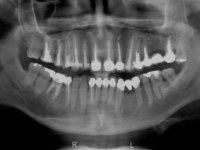

Paciente do sexo masculino, com 42 anos de idade, não fumador. Apresentava uma reabilitação metalo -cerâmica feita há mais de 10 anos com exposições radiculares e infiltrações. No maxilar superior apresentava uma coroa no 1.1,uma ponte de dois elementos no 2.1 e 2.2.e uma ponte de 4 elementos nos dentes 2.4,2.5,2.6 e 2.7 com o 2.6 como pôntico. Os dentes 1.6/1.5/1.4/1.3/1.2/1.1/2.1/2.2/2.3/2.4/2.5 e 2.7 apresentam tratamento endodôntico radical com o 2.4/2.5 e 2.7 a necessitarem de ser refeitos. No maxilar inferior apresentava uma ponte metalo-cerâmica de 4 elementos nos 4 incisivos e uma ponte de 3 elementos (3.3 e 3.4) com um dente supranumerário como pôntico. Os dentes 4.6/4.5 e 4.2 apresentavam tratamento endodôntico com o 4.2 a necessitar de ser refeito. Os dentes 4.3 e 4.4 apresentavam extensas cáries linguais com algum comprometimento mesial. As peças protéticas apresentavam-se infiltradas com exposição radicular associada. Apresentava uma D.V.O. diminuída e uma mordida cruzada lado direito. O paciente tinha uma satisfatória saúde periodontal e uma boa higiene oral.

Foi proposto ao paciente fazer uma reabilitação total com infraestruturas em zircónia revestidas a cerâmica. No maxilar superior, seriam realizadas 6 coroas (1.3/1.2/1.1/2.1/2.2/2.3), uma ponte de 3 elementos (1.4/1.5/1.6) e uma ponte de 4 elementos (2.4/2.5/2.6 e 2.7). No maxilar inferior, foram propostas 7 coroas (4.3/4.2/4.1/3.1/3.2/3.5 /3.6) e duas pontes (4.4//4.5/4.6) e (3.3/3.4#/3.4).O objetivo seria subir a D.V.O., descruzar a mordida do lado direito, eliminar as infiltrações e as exposições radiculares e reabilitar o paciente com estruturas protéticas com aspeto mais natural.

A primeira acção terapêutica foi tentar melhorar o tratamento endodôntico dos dentes (2.4/2.5/4.2)). A sua manutenção em boca seria condicionada pelo sucesso desta intervenção. Seguidamente foram feitas impressões em alginato e registo inter-maxilar em silicone para confeção em laboratório de uma ponte provisória em acrílico com reforço. O objetivo desta ponte provisória seria ensaiar o aumento da D.V.O. e descruzar a mordida do lado direito. Foi utilizado um monobloco de 13 dentes com o dente 2.6 com o pôntico. As coroas e as pontes foram removidas e os remanescentes coronários foram repreparados. A ponte provisória foi rebasada primeiramente com acrílico auto-polimerizável e de seguida com resina composta. Após 2 semanas de permanência em boca, foram feitas as impressões para confeção da ponte provisória inferior também realizada em laboratório. Especial cuidado foi colocado na remoção das coroas antigas, sendo feito primeiramente um corte axial que permitiu que fossem removidas de uma forma menos traumática. A temporização foi feita durante 8 semanas, permitindo que os tecidos gengivais estabilizassem posicionalmente. As impressões definitivas foram realizadas após afastamento gengival utilizando a técnica do fio único impregnado. Foi utilizada a técnica de dupla mistura com dupla viscosidade (putty soft e light).Simultaneamente foi realizada a recolha das relações inter-maxilares e o registo com arco facial. Foram confecçionados os modelos de trabalho e feita a sua correta montagem em articulador semi-ajustável. Em seguida foram feitas infra estruturas em zircónia que posteriormente foram revestidas por cerâmica. A prova de “biscoito” foi realizada em boca para avaliação estética e funcional sendo também avaliado o seu assentamento e ajuste. A reabilitação definitiva foi cimentada em boca utilizando um cimento de ionómero de vidro reforçado por resina.